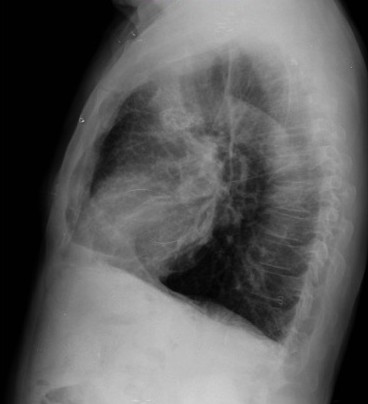

CASO: Febrícula y tos de 4 días de evolución.

Hallazgos:

- En la placa PA se observa una asimetría en los hilios pulmonares, el hilio izquierdo tiene una densidad aumentada.

- Tras examinar la placa lateral se observa un aumento de densidad en la columna que puede ser compatible con una condensación, es el signo de la desnificación vertebral.

SIGNO DE LA DENSIFICACIÓN VERTEBRAL: En la radiografía lateral normal, la densidad de la columna torácica tiende a disminuir desde la parte superior hasta el diafragma; la alteración de ese patrón por la presencia de una densidad superpuesta a la columna, indica la existencia de una consolidación pulmonar. Este signo adquiere especial valor cuando en la proyección posteroanterior la consolidación está oculta en el espacio retrocardíaco o en la base pulmonar.